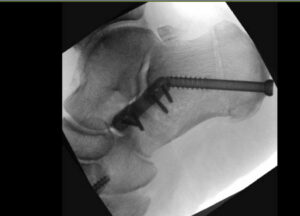

Kotiutumispäivän aamuna oksensin ensimmäisen ja ainoan kerran. Se johtui varmaan lääkkeistä ja lyhyistä yöunista. Puolenpäivän aikaan kipsini vaihdettiin. Ortopedi oli mukana asettamassa jalan oikeaan asentoon. Hän sanoi, että blokkipuudutus toimii vieläkin, muuten en antaisi hänen koskea jalkaani. Hoitaja oli sanonut minulle, että puudutuksen kestoaika on yksilöllinen. Se kestää 24-36 tuntia. Minulla kesti yli 48 tuntia. Leikkaussalissa rakennettu kipsi oli laitettu niin, että nilkka oli kääntyneenä hiukan sisäänpäin. Uskon, että sillä haluttiin varmistaa, ettei uusi jänne katkea. Huomasin nilkan oudon asennon ensimmäisenä yönä ja kysyin hoitajalta, oliko kipsi vahingossa väärässä asennossa. Hän kuitenkin vakuutti sen olevan juuri niin kuin pitää.